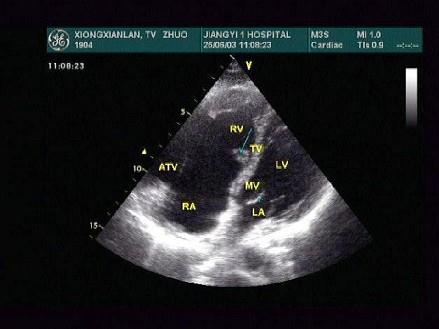

问题 男28岁,胸部疼痛1周余,神清,心律齐,超声心动图如下,根据图片应提示?(?)

选项 A.单心室 B.心内膜垫缺损 C.三尖瓣上移 D.三尖瓣下移 E.三尖瓣狭窄

答案 D